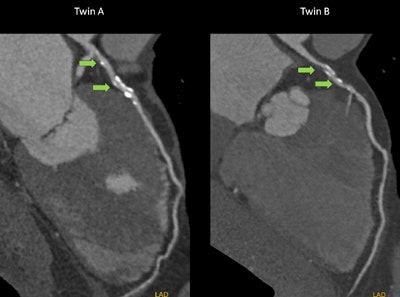

Showing a slide of a CT scan of two monozygotic twins' hearts, he explained that the hearts are very similar, but some subtle differences are visible, for example it can be seen that Twin B has a more tortuous coronary vessel.